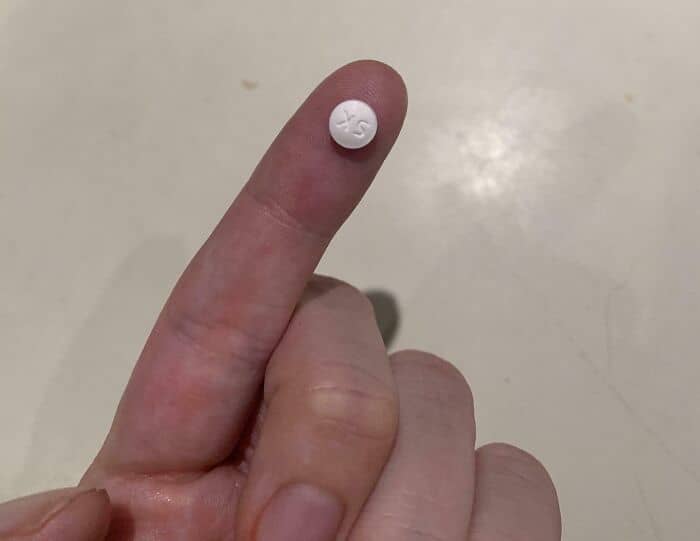

#47 Each Of These Teeny Pills Costs $40

So glad my family has health insurance, but how do people without health insurance afford medicine in the U.S?

Can’t imagine not having health insurance.